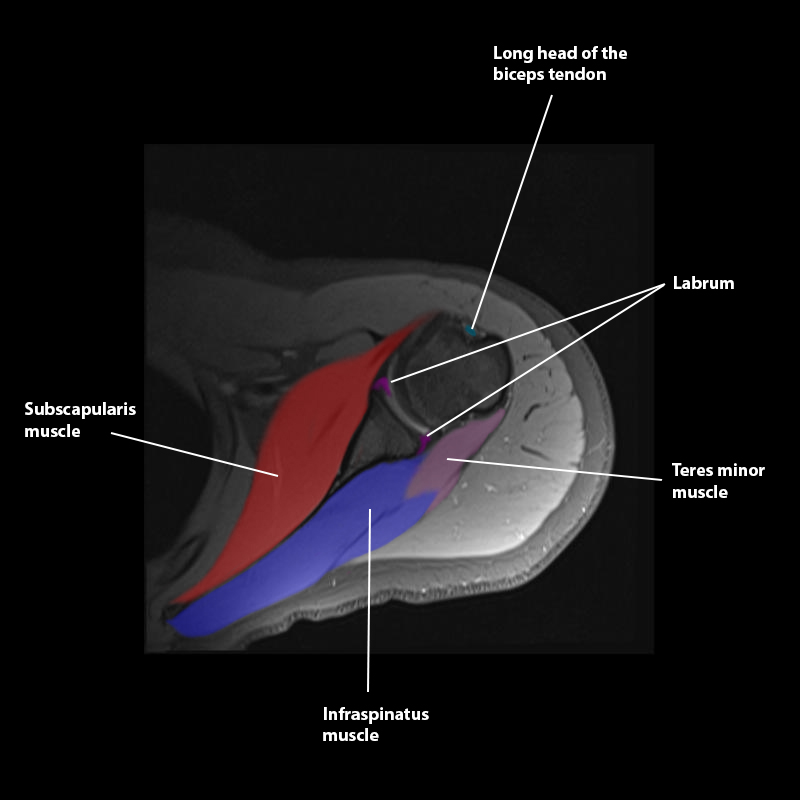

Shoulder MRI Anatomy